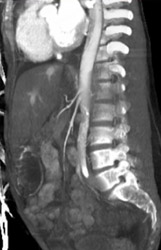

Clot in Inferior Vena Cava (IVC)